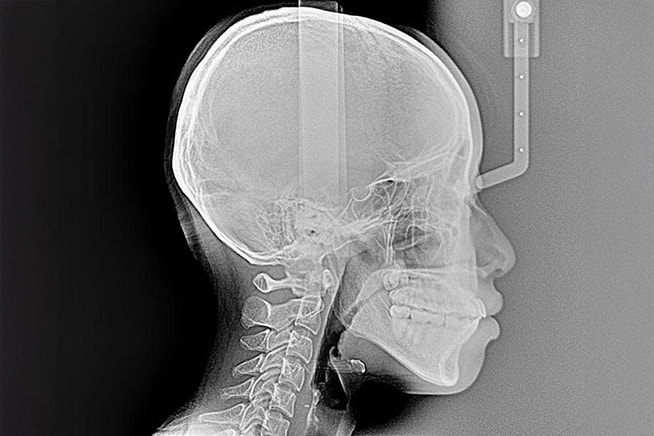

矯正専用レントゲン

(セファロ)

頭部の骨格や歯の位置関係を正確に計測できるため、より的確な矯正診断・治療計画の立案に役立ちます。